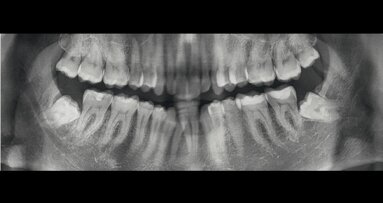

La paziente, donna di 26 anni, presentava agenesia bilaterale degli incisivi laterali superiori. Affermava di voler risolvere la problematica il più velocemente possibile per motivi di natura sia psicologica sia economica, esprimendo il desiderio di ottenere una riabilitazione funzionale ed estetica tramite un intervento finalizzato alla realizzazione di una protesi fissa. È stato quindi prospettato un approccio terapeutico multidisciplinare basato su trattamento ortodontico per migliorare l’allineamento e ottimizzare lo spazio per il posizionamento implantare. Dopo accettazione e firma del consenso, si è proceduto al trattamento ortodontico fisso. In una prima fase, due elementi provvisori a pura funzione estetica sono stati apposti all’apparecchio ortodontico (Fig. 1a). Ottenuto il risultato ortodontico a distanza di 12 mesi (Fig. 1b), si è potuto procedere con l’inserimento di impianti B1ONE (IDI Evolution) a diametro ridotto.

Fig. 1_Presentazione del caso. Il paziente presenta agenesia bilaterale degli incisivi secondari superiori; a) trattamento conservativo con provvisori in resina solidarizzati all’apparecchio ortodontico e a sola funzione estetica; b) trattamento ortodontico per l’ottimizzazione del piano occlusale e dello spazio mesio-distale.